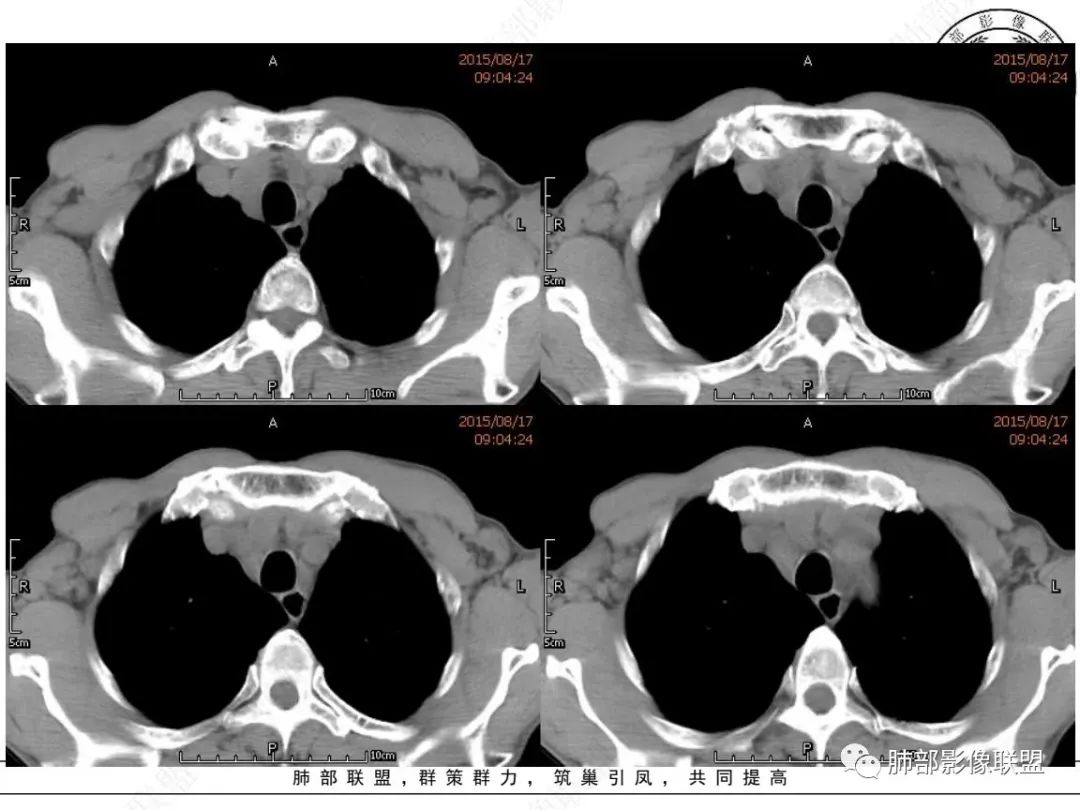

放射小白:老年男性,右侧肺门可见团块状占位包绕气管,气管受压变窄,纵隔见巨大团块状占位,另纵隔可见肿大淋巴结,增强肺门及纵隔肿块强化不明显,内部可见血管影,周围结构只是受压移位,另颌下淋巴结穿刺慢性淋巴结炎,首先考虑小细胞癌,鉴别淋巴瘤、结节病。

宇宙:右肺下叶小结节,右肺门及中后纵膈淋巴结肿大融合,强化均匀,主支气管、中间段及下叶支气管受压变窄,右下肺静脉受压变窄,考虑小细胞癌,鉴别淋巴瘤

丽:老年男性,纵隔及肺门多发肿大淋巴结,相互融合呈团块状,包绕支气管官腔,呈针尖样狭窄,增强后轻度强化,考虑小细胞肺癌

放射线:纵隔及肺门淋巴结肿大相互融合呈冰冻纵膈,支气管受压变窄呈针孔样,老年男性吸烟患者,考虑小细胞肺癌。

采莲:老年男性,有吸烟史,双颈部肿块,双肺纵隔淋巴结多发淋巴结肿大并融合成块,气管及右肺下叶支气管受压狭窄,考虑恶性,淋巴瘤可能,鉴别小细胞肺癌。

崔少钢:老年男性,有吸烟史,右肺下叶背段示小结节,纵隔、腋窝及右肺门淋巴结节肿大,气管受压狭窄,后纵隔软组织内示血管走行,考虑小细胞>淋巴瘤。

我只是邓较瘦:晨读老年男性,长期吸烟。右肺门、纵隔多发肿大淋巴结、融合成团块,中间支气管、右肺下叶支气管受压变窄,增强扫描强化程度较轻,血管包埋。另两侧腋窝亦见多发肿大淋巴结。常规恶性没问题,小细胞?淋巴瘤?但是於老师的病例总感觉没那么简单。

谢加平:纵隔内中后纵隔及右肺门淋巴结肿大,形成大肿块,整体密度均匀,并轻度强化,见“血管飘浮”征,包绕气管分叉及右主支气管及中间段支气管明显受压狭窄,并包埋右肺门血管束,无侵蚀破坏,右肺动脉后壁见压迹影,右肺下叶背段有阻塞性炎症,首选淋巴瘤,支气管超声内镜活检,明确诊断!